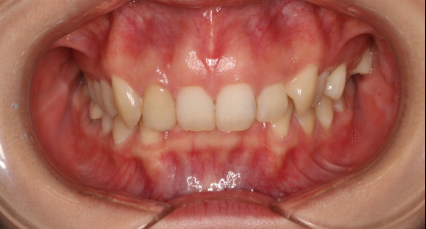

正頜手術(shù)治療骨性齙牙的風(fēng)險